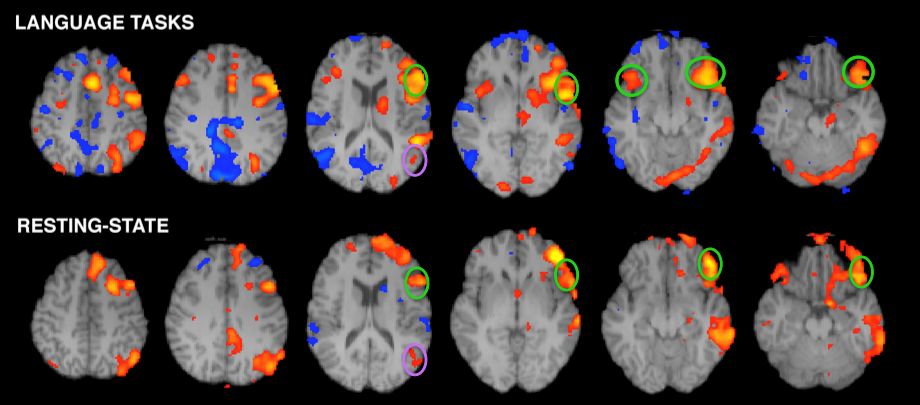

Em imaging

Em imaging 57 фотографий